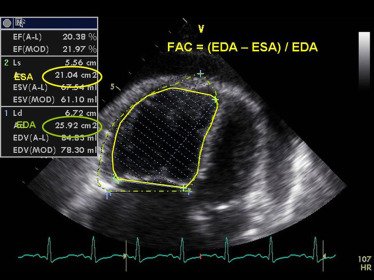

But CAD doesn't only affect the left ventricle.

Right ventricular infarction can occur, especially with right coronary artery occlusion.

Echo findings may include:

🔵 RV wall motion abnormalities

🔵 Reduced TAPSE

🔵 RV dilation Calculation of fractional area change (FAC) from tracings of end-diastolic area (EDA) and end-systolic area (ESA) of the right ventricle.